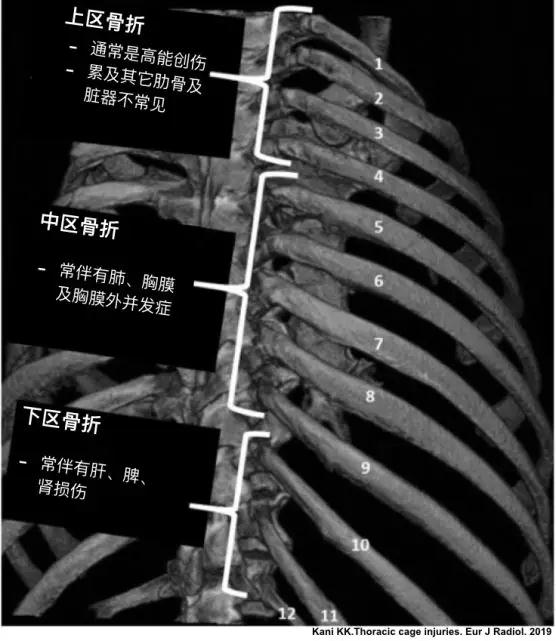

胸部外傷的急診患者 首先要想到這4類診斷 急診醫學影像 壹讀

胸部外伤看肋骨 诊断中这个建议最好写上 影像ppt

肋骨骨折 你漏诊了吗 螺旋ct三维重建在胸廓骨折中的应用价值

肋骨骨折是個坑 就看挖的深不深 每日頭條

肋骨骨折 你漏诊了吗 螺旋ct三维重建在胸廓骨折中的应用价值